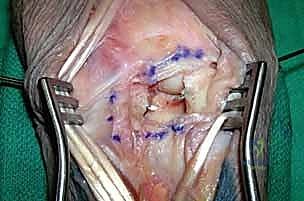

Ligament Repair: Restoring Intrinsic Stability

Surgeon: "With our bony architecture restored, our next critical step is ligamentous repair. First, we need to ensure absolute anatomic carpal realignment. Sometimes, despite the initial reduction, minor rotational malalignments can persist. We can use 0.045-mm Kirschner wires as 'joysticks' introduced into the scaphoid, lunate, and triquetrum to finely adjust their positions and achieve perfect alignment."

Surgeon: "Once alignment is confirmed, we'll advance those initial K-wires we placed through the scaphoid and triquetrum into the lunate. These provide critical transosseous stability across the scapholunate and lunotriquetral intervals."

Surgeon: "Now, let's turn our attention to the intercarpal ligaments. In lesser arc injuries, both the scapholunate and lunotriquetral ligaments are typically disrupted. In transscaphoid perilunate dislocations, the proximal pole of the scaphoid often remains attached to the lunate with an intact scapholunate ligament, but the radial side of the carpus is unstable due to the scaphoid fracture."

Surgeon: "Most often, these ligaments avulse from the scaphoid and the triquetrum. Therefore, we'll use small (about 2 mm) suture anchors with nonabsorbable suture (2-0 to 3-0) for reattachment. I'll place the anchors directly into the bony substance of the scaphoid and triquetrum where the ligaments have avulsed. It's crucial to avoid our previously placed Kirschner wires during anchor insertion."

Surgical Warning: Ensure proper tensioning of the ligament repair. Over-tensioning can lead to stiffness, while under-tensioning will result in persistent instability. Aim for a tension that mimics the contralateral wrist's natural laxity.

Surgeon: "What if the intercarpal ligaments are beyond direct repair due to severe comminution or poor tissue quality? In such cases, suture anchors may be unnecessary or ineffective. We then rely primarily on extrinsic capsuloligamentous healing, augmented by our K-wire stabilization, to establish stability. This underscores the importance of a robust capsular repair."

Volar Capsuloligamentous Repair:

Surgeon: "Once the carpal tunnel contents are retracted, we'll gain visualization of the volar capsuloligamentous structures and the characteristic semilunar rent, often found through the space of Poirier. We'll meticulously repair these volar capsuloligamentous injuries using nonabsorbable sutures to further stabilize the carpus. This volar repair is essential for long-term stability and preventing recurrent volar instability."